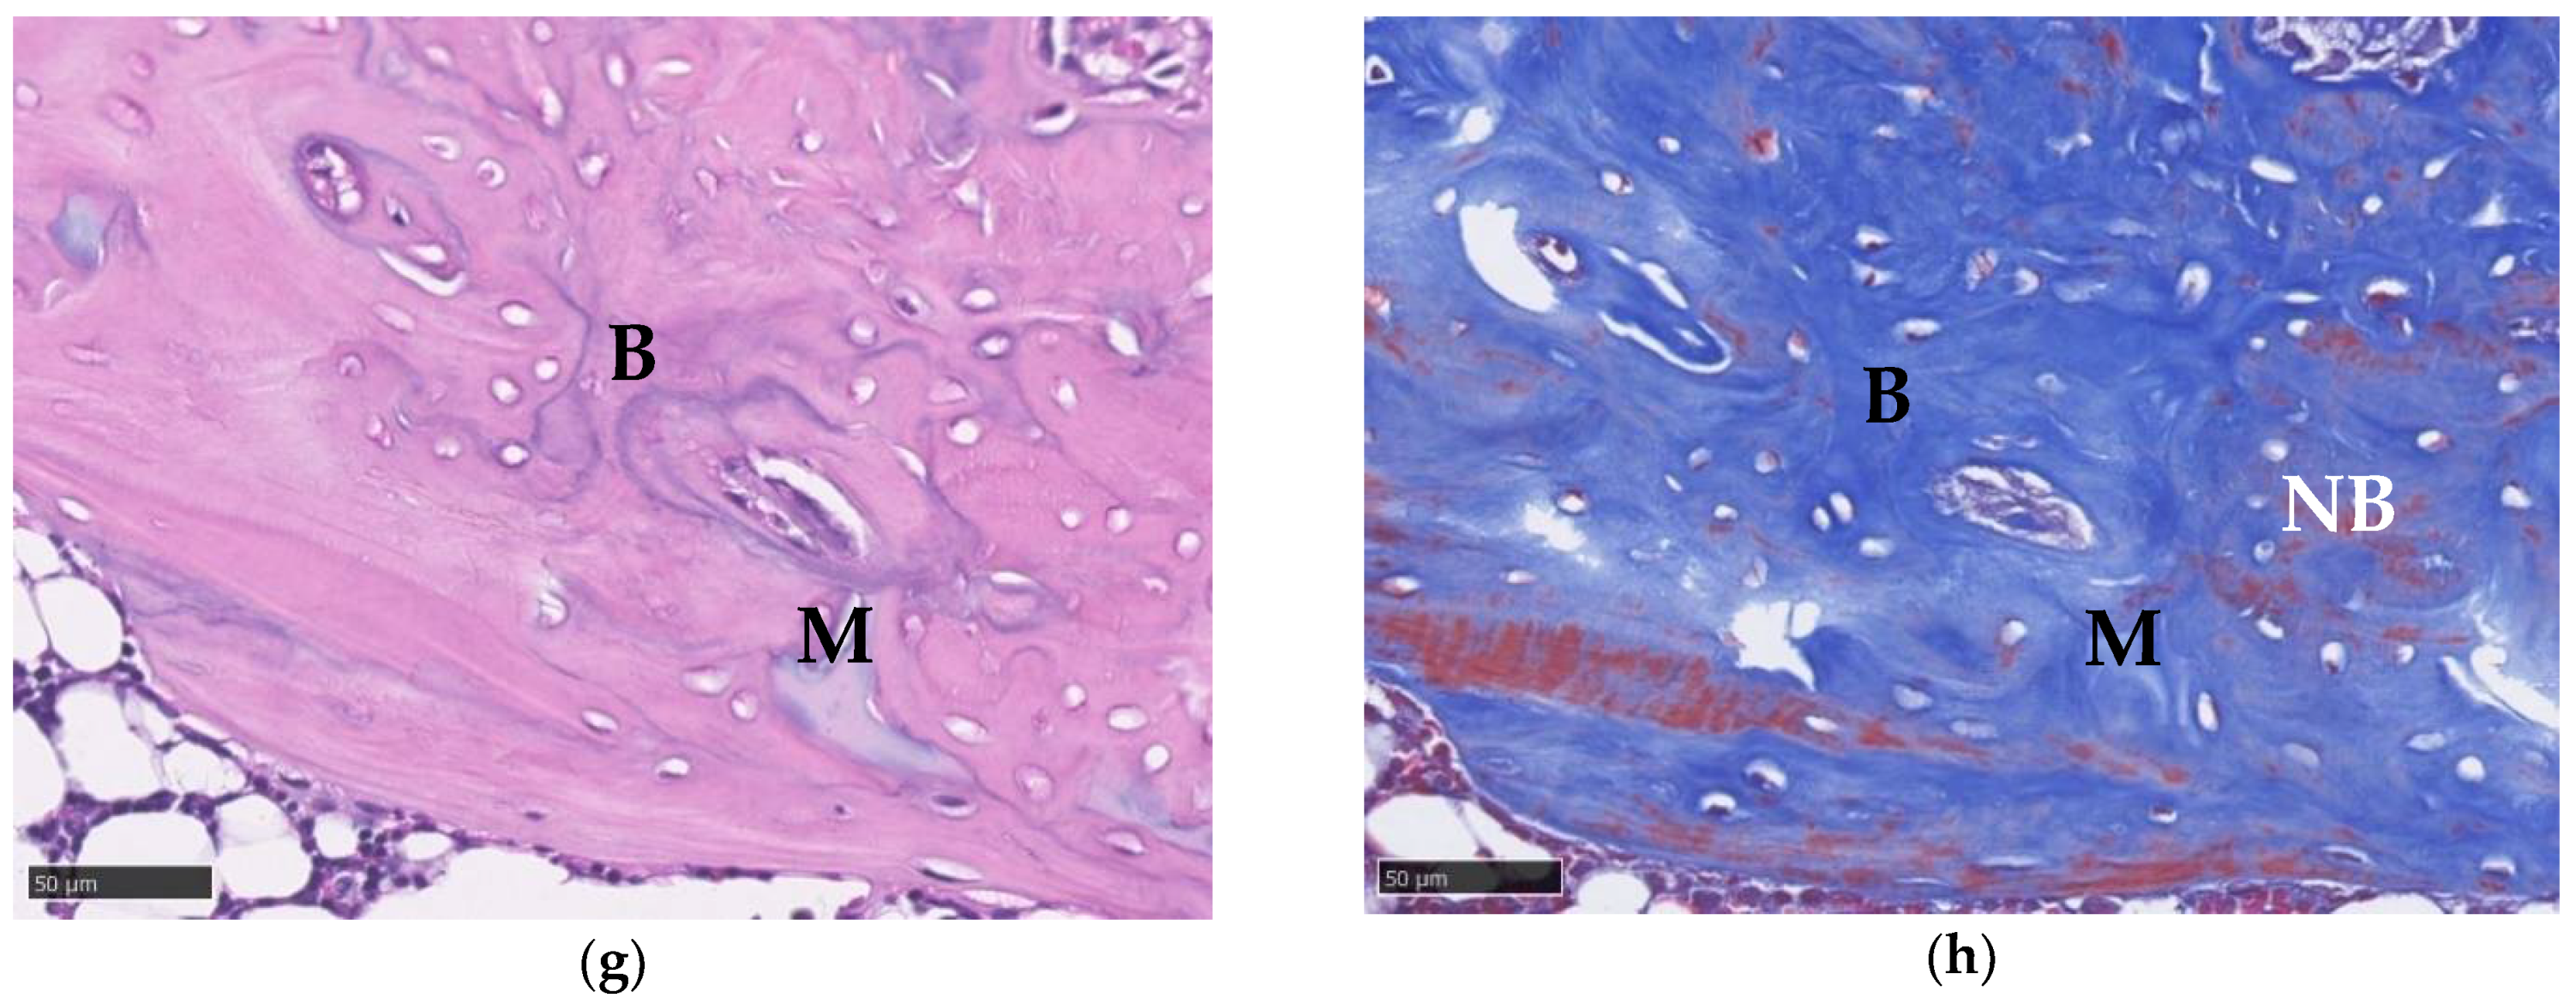

3.10. Histological Imaging